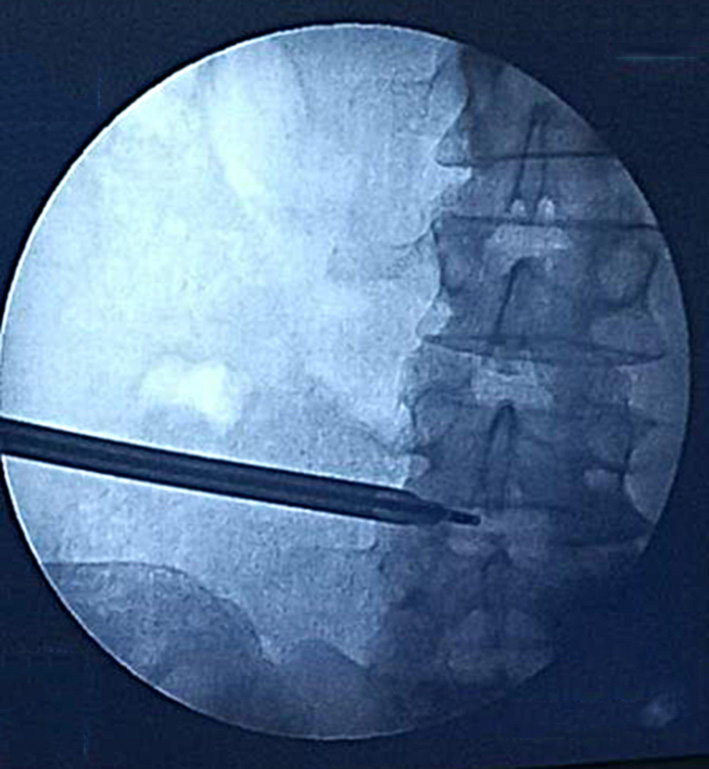

A transforaminal endoscopic microdiscectomy of the L4-L5 intervertebral disc on the right was performed. Fig. 7 shows fluoroscopic guidance of the endoscope port placement in the specified area of the L4-L5 intervertebral space on the right.

A

B

Fig. 7. Port placement: A – lateral projection; B – straight projection